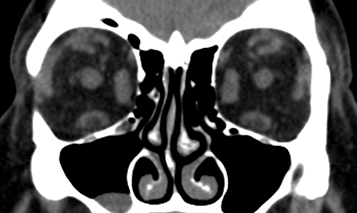

Imaging: CT of the orbit (axial and coronal views without contrast) is performed when the presentation is atypical (e.g., most cases of unilateral proptosis or any bilateral proptosis without upper eyelid retraction), or in the presence of severe congestive orbitopathy or optic neuropathy. CT in TED varies from patient to patient. In patients with restrictive strabismus and minimal proptosis (myogenic variant), imaging will show thickened EOMs without the involvement of the associated tendons and apical crowdingthe loss of fat signal in the orbital apex because of enlarged EOMs (see Figure 7.2.1.2). In patients with full or nearly full extraocular motility, severe proptosis, and exposure keratopathy (lipogenic variant), increased fat volume with minimal muscle involvement is typical.